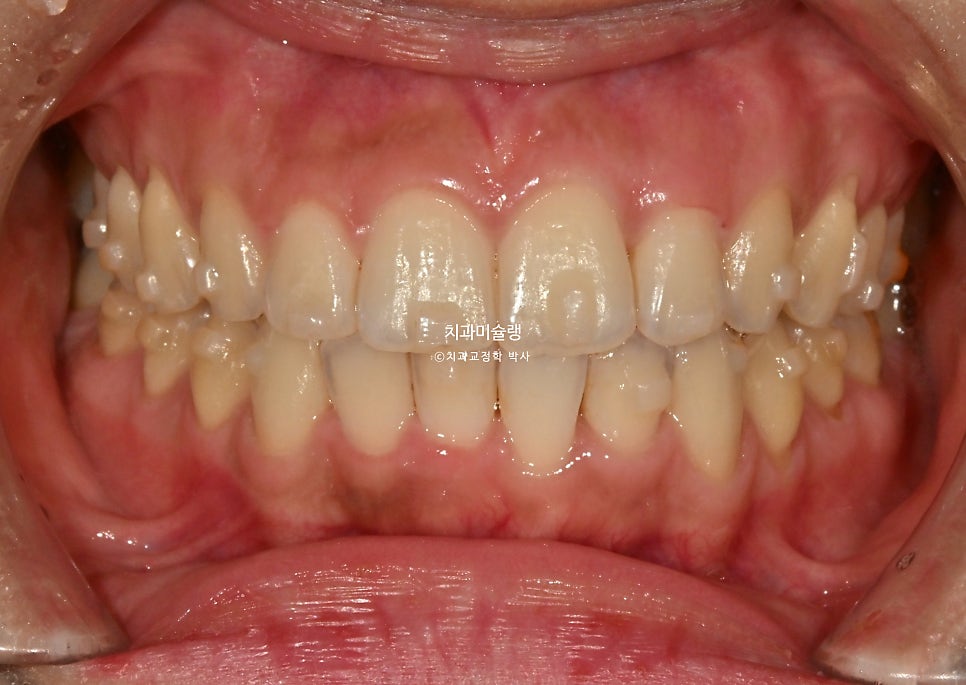

첫세트 14개 장치를 4달에 걸쳐 모두 낀 후 모습입니다.

중심선, 배열 모든게 좋습니다. 사전에 계획된 치간삭제로 블랙트라이앵글은 보이지 않습니다.

좋았던 어금니 교합은 그대로 잘 유지되었죠.

앞니 배열에서 아쉬는 부분을을 디테일하게 개선하기 위해 추가장치 제작에 들어갔습니다.